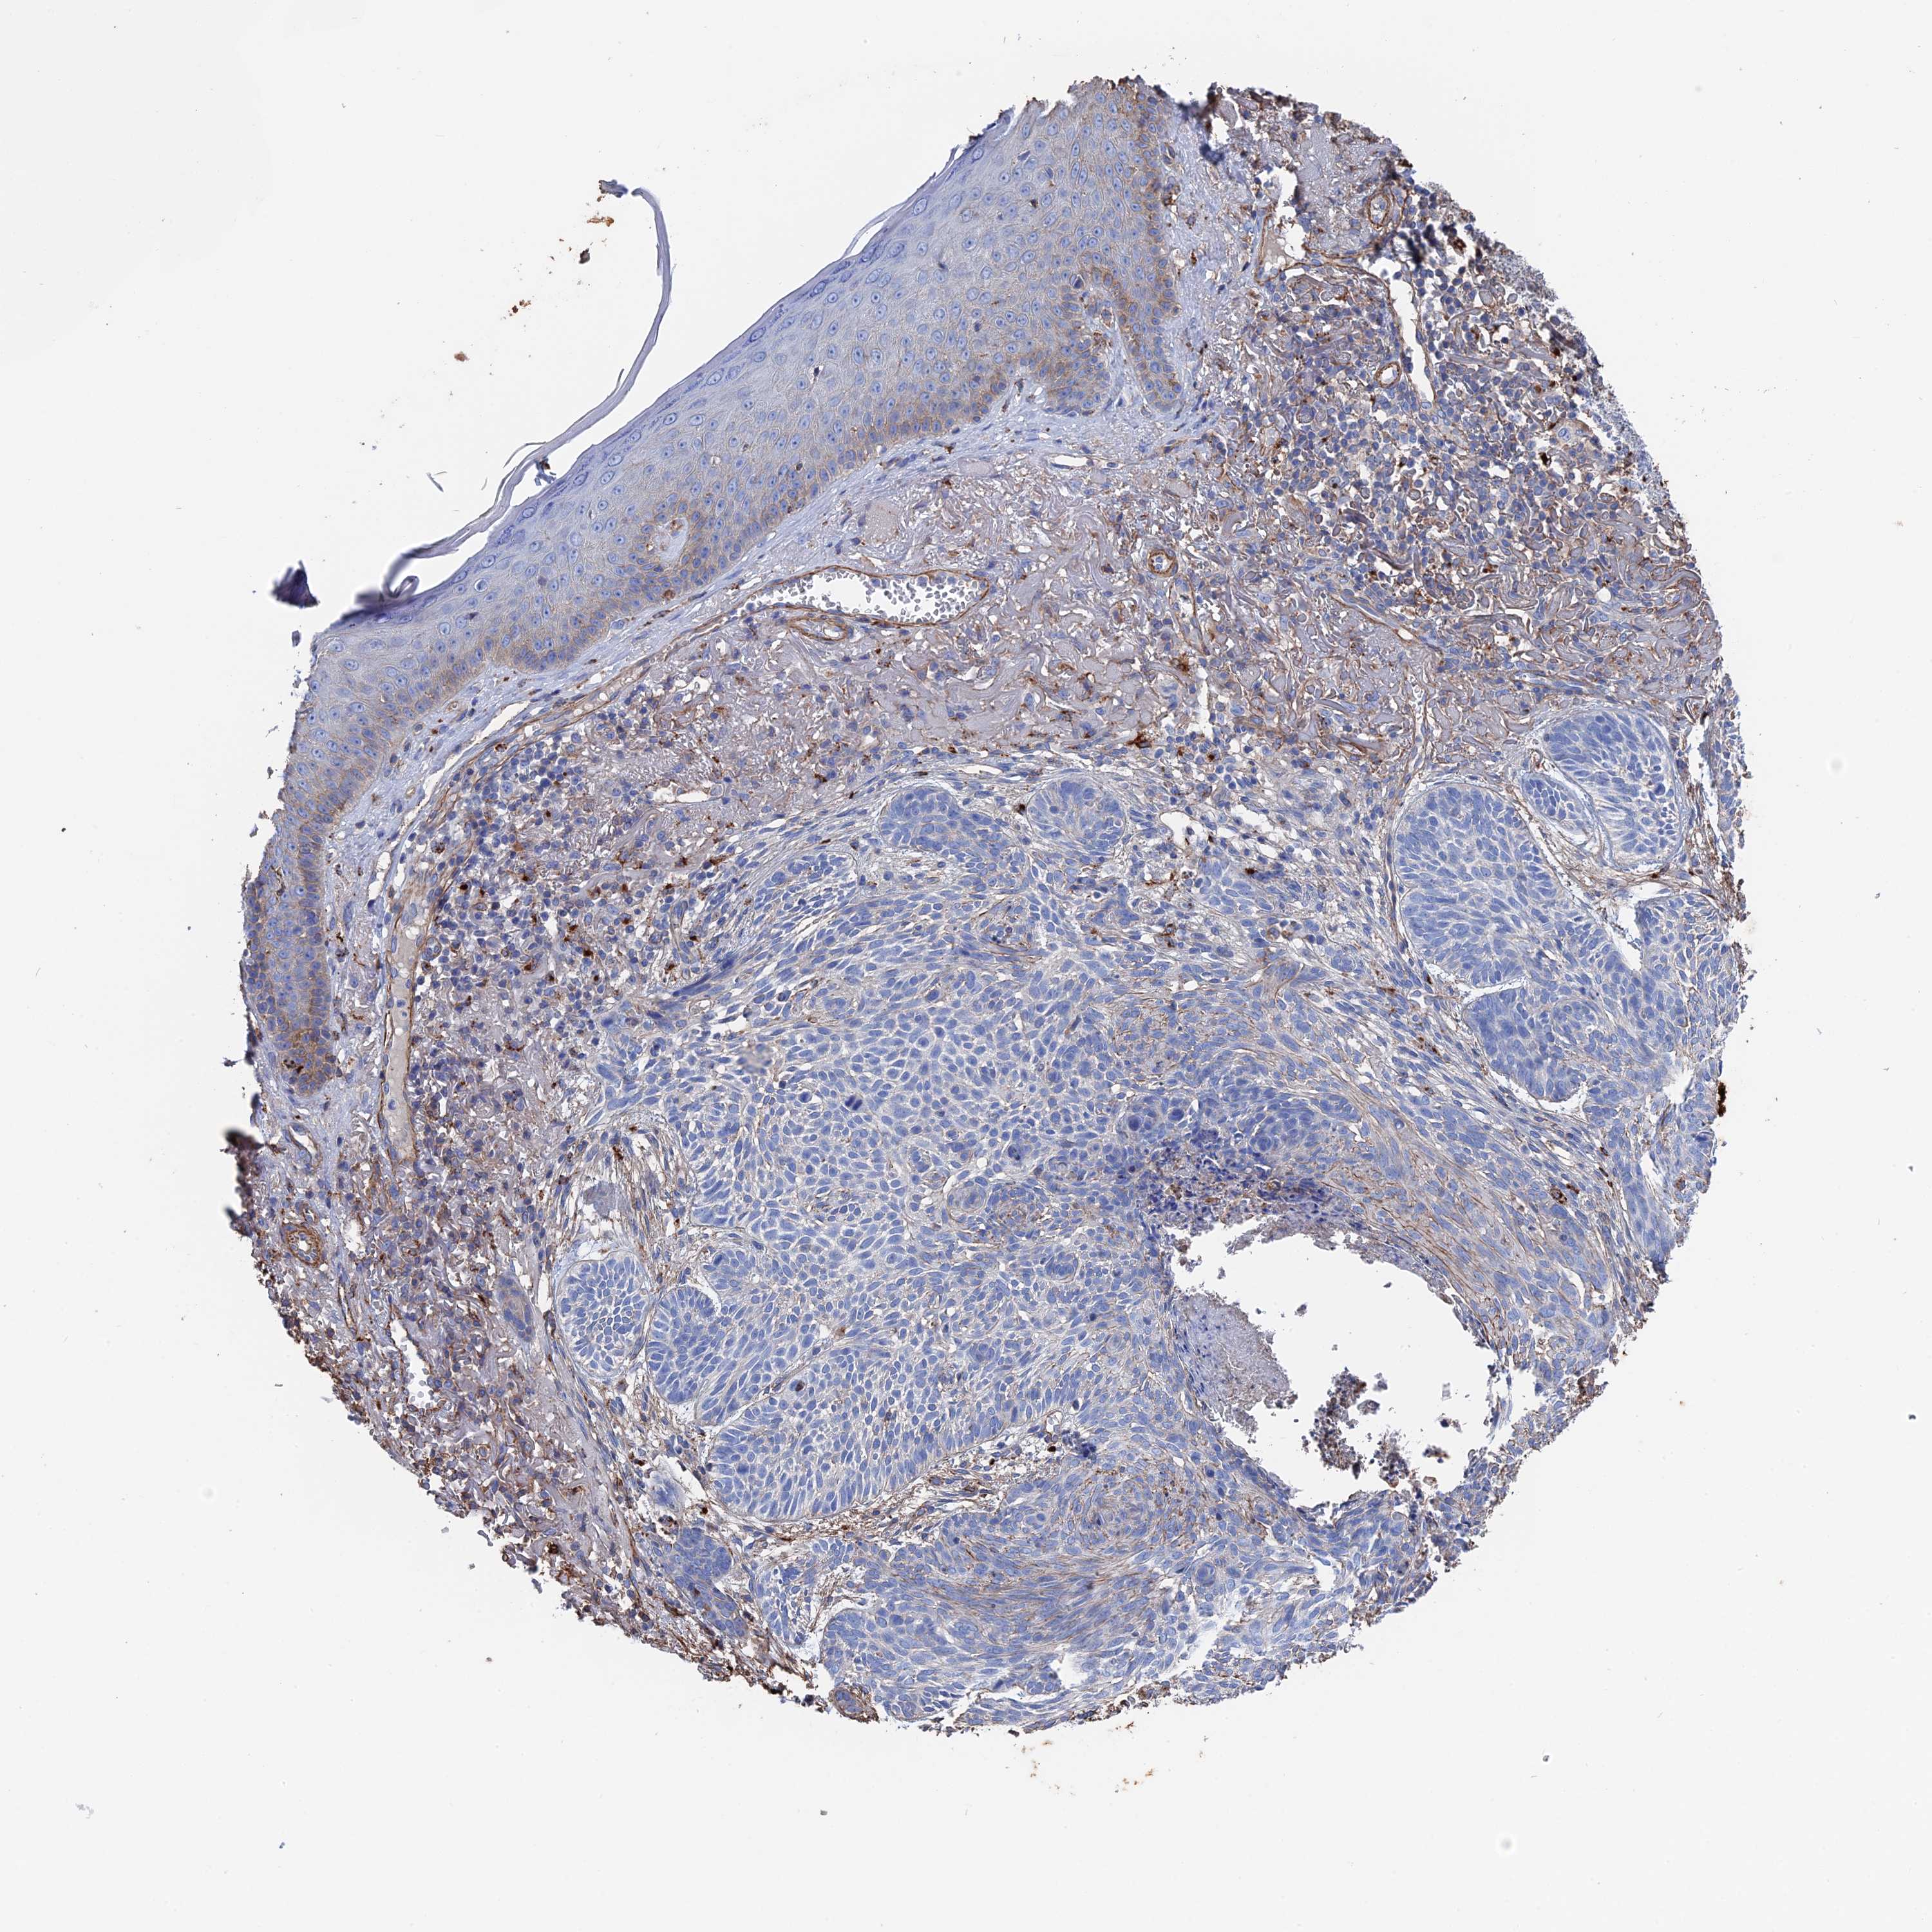

CANCER SKIN CANCER Show tissue menu

Basal cell and squamous cell cancer

SKIN CANCER - Protein expressioni

A mouse-over function shows sample information and annotation data. Click on an image to view it in a full screen mode. Samples can be filtered based on level of antibody staining by selecting one or several of the following categories: high, medium, low and not detected. The assay and annotation is described here.

Each image is clickable and will lead to virtual microscopy that enables deeper exploration of all samples and also displays staining intensity scores, fraction scores and subcellular localization as well as patient and tissue information for each sample.

Antibody HPA040839

Staining

High

Medium

Low

Not detected

Intensity

Strong

Moderate

Weak

Negative

Quantity

>75%

75%-25%

<25%

None

Location

Nuclear

Cytoplasmic/membranous

Cytoplasmic/membranous,nuclear

Basal cell carcinoma

Squamous cell carcinoma, NOS

Squamous cell carcinoma, metastatic, NOS